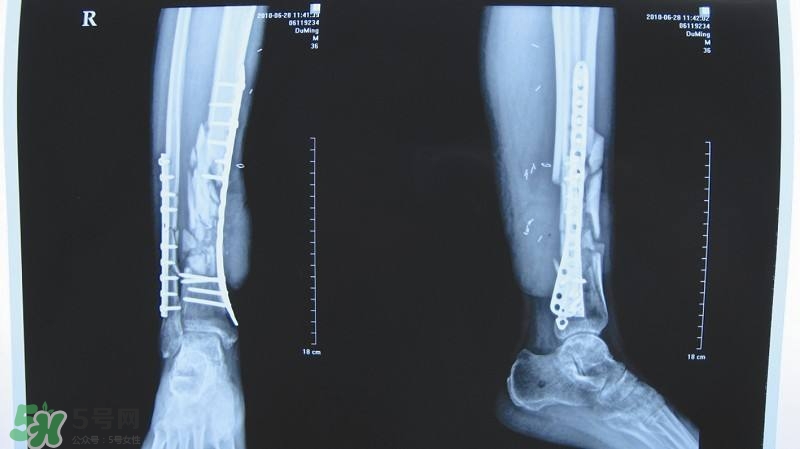

》的解答。1.骨折后吃什么食物好得快2.骨折吃什么好得快?骨折后注意事项3.骨折了吃什么食物比较好恢复的快4.骨折后期吃什么食物恢复快1.误解区:大多数人认为骨折或骨头粉碎,只有吃骨头汤就好了。

3.治疗骨折分个阶段:初级、中期、后期个阶段。